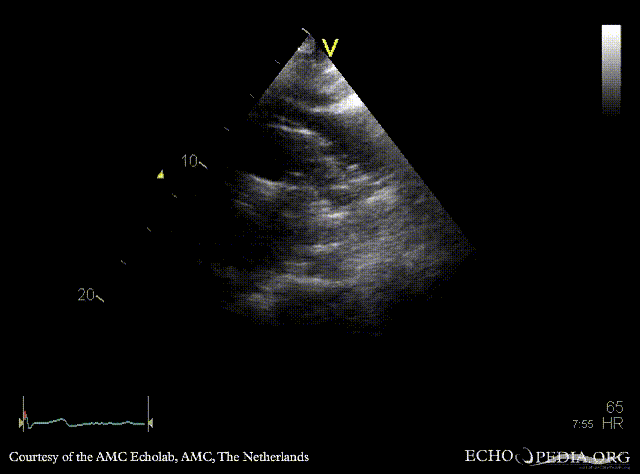

E00645.gif E00646.gif

Suprasternal view Suprasternal view with Color Doppler, open ductus Botalli